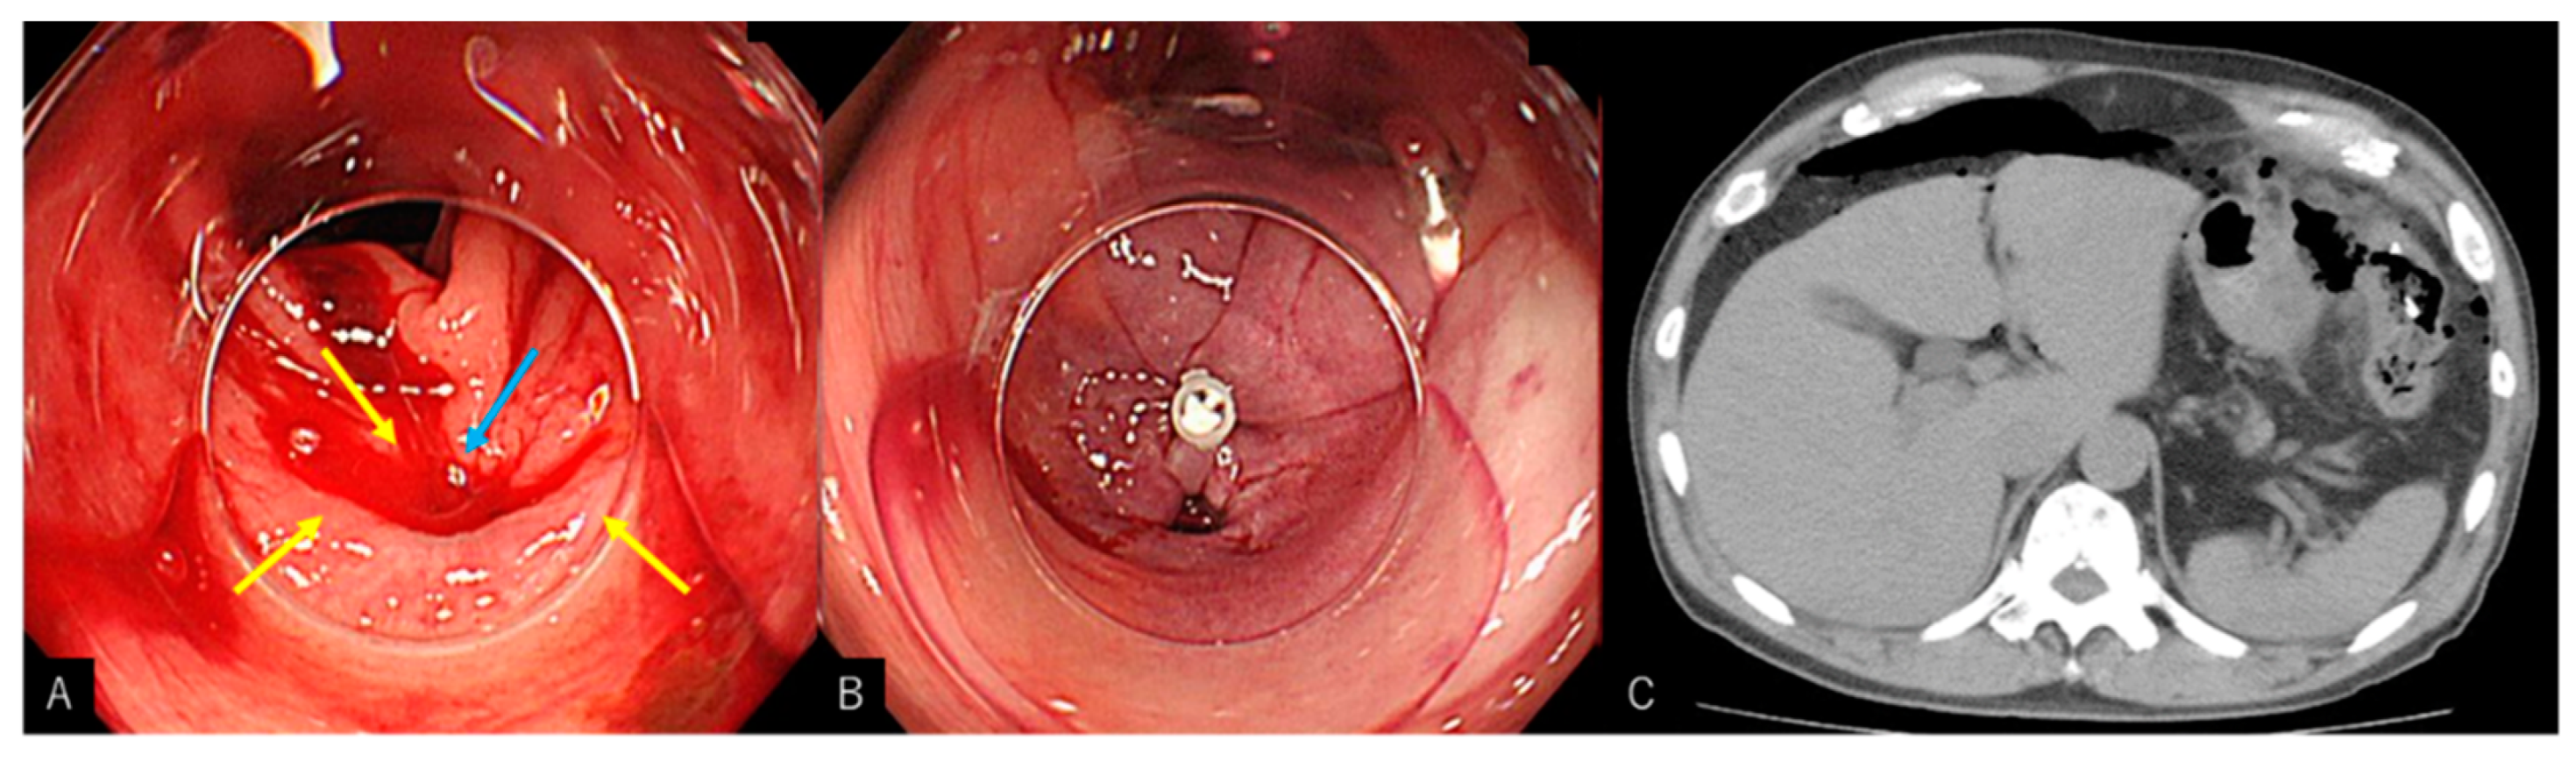

2.2. Procedure